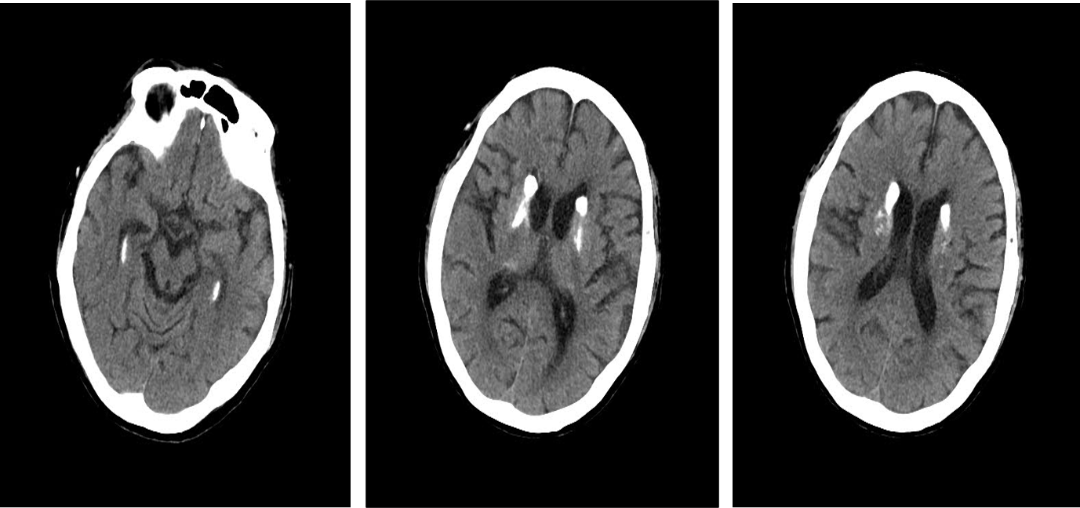

入院影像检查

导丝怎么扩重磅!NOVA颅内药物球扩支架湖北首例植入!_https://www.jmylbn.com_新闻资讯_第4张

DWI

MRI(T2Flair)

导丝怎么扩重磅!NOVA颅内药物球扩支架湖北首例植入!_https://www.jmylbn.com_新闻资讯_第5张

MRA

重要影像结论:左侧大脑半球内侧多发陈旧性梗死灶,左侧颈内动脉C4段重度狭窄。